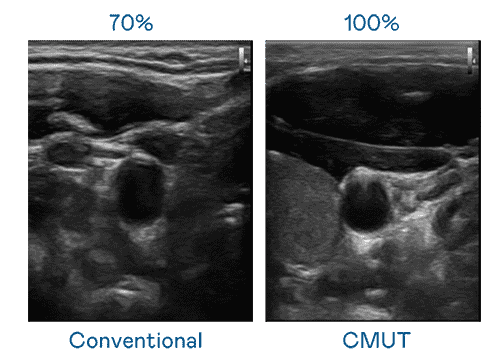

CMUT 技术是一种用电容式微机电元件来产生超音波讯号的技术。。与传统 PZT 压电式技术相比,,,,CMUT 频宽增加 30%,,,,更宽频的超音波讯号让影像解析度大幅提升,,,是实现高影像品质医疗超音波扫描、、促进精准医疗发展的关键技术。。。。

大频宽带来超清晰影像

超音波影像的解析度高低,,首先取决于探头能发出的讯号频宽。。。EBpay CMUT 可提供高清晰的超音波讯号,,,,提供高频宽、、高灵敏度、、、影像纹理细节更高的超音波影像,,协助医护人员缩短影像判读时间及利用精准的医疗影像进行诊断。。。。